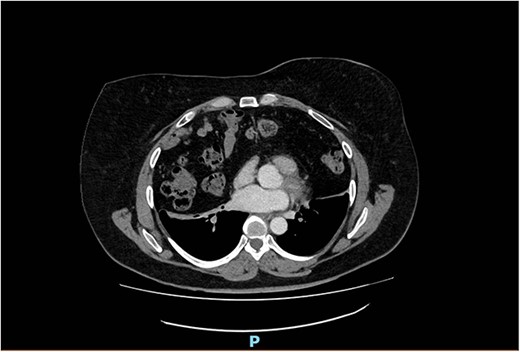

The spirometry results from her General Practitioner showed a restrictive pattern with FVC of 2.08L (55% predicted), FEV1 of 1.62L (54% predicted) and FEV1/FVC ratio of 0.78 (96% predicted). Her chest X-ray demonstrated a large hiatus or congenital hernia (Fig. 1). Subsequent computed tomography (CT) of the chest, abdomen and pelvis showed a large 88 × 48-mm defect of the anterior diaphragm consistent with MH. Hernial contents extended to the superior mediastinum and were primarily large bowel and omentum, with no intestinal obstruction (Figs 2–4).

Arterial contrast CT of the chest. Axial slice at the T4/5 level showing herniation of large bowel, small bowel and omentum into the chest cavity. The defect in the anterior diaphragm measures 88.2 mm × 48.2 mm. Of note is the significant reduction in the size of the lung fields.